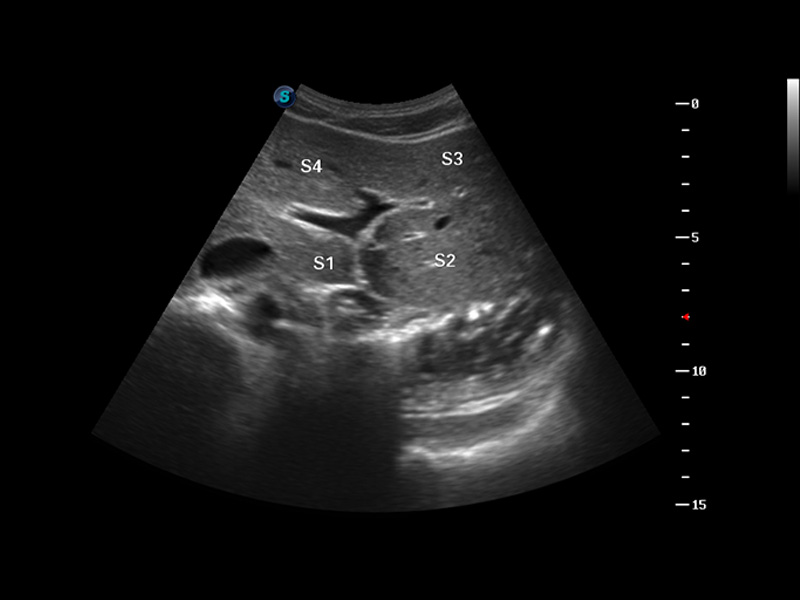

S8 EXP便攜式彩色多普勒超聲診斷儀是開立醫(yī)療研發(fā)的高端全身應(yīng)用型便攜彩超。高通道的VIS平臺融合可視化(Visual)、智能化(Intelligent)和人性化(Smart)的特點,配以開立醫(yī)療自主研發(fā)生產(chǎn)的探頭大家族,使您能夠快速、準確的獲得病人信息,提高工作效率的同時減輕疲勞。

成像技術(shù)

多波束形成器

μ-Scan微米成像

諧波成像

實時寬景成像

空間復(fù)合成像

3D/4D成像